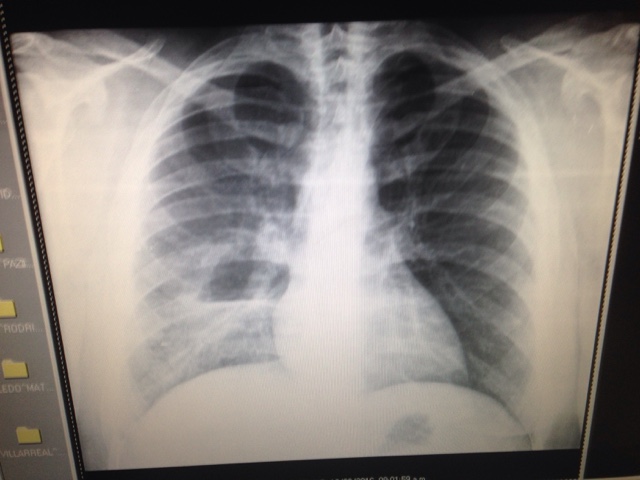

Hipertension pulmonar tromboembolica

Paciente femenina de 25 años de edad con disnea de esfuerzo y tos no productiva desde hace 2 meses, con soplo sistolico sin ganglios supraclaviculares que llega con rx de torax simple. El ecocardiograma revelo presion de arteria pulmonar de 34 mmhg y derrame pericardico y en la tomografia del torax con contraste hay derrame pericardico y tumoracion por encima del arco aprtico y trombo en arteria pulmonar derecha con reduccion del calibre de arteria piñmonar